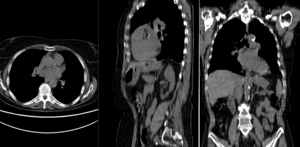

rigidrigid

BSpline registration of full volumes. 11 x 11 x 7 gridBSpline registration of full volumes. 11 x 11 x 7 grid